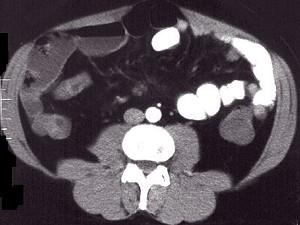

问题 女,30岁,右下腹痛,腹泻便秘交替出现,消瘦乏力,血沉加快,X线检查如图,最佳的诊断是 ( )

选项 A.小肠癌 B.小肠结核 C.小肠克罗恩病 D.结肠癌 E.阑尾炎

答案 C